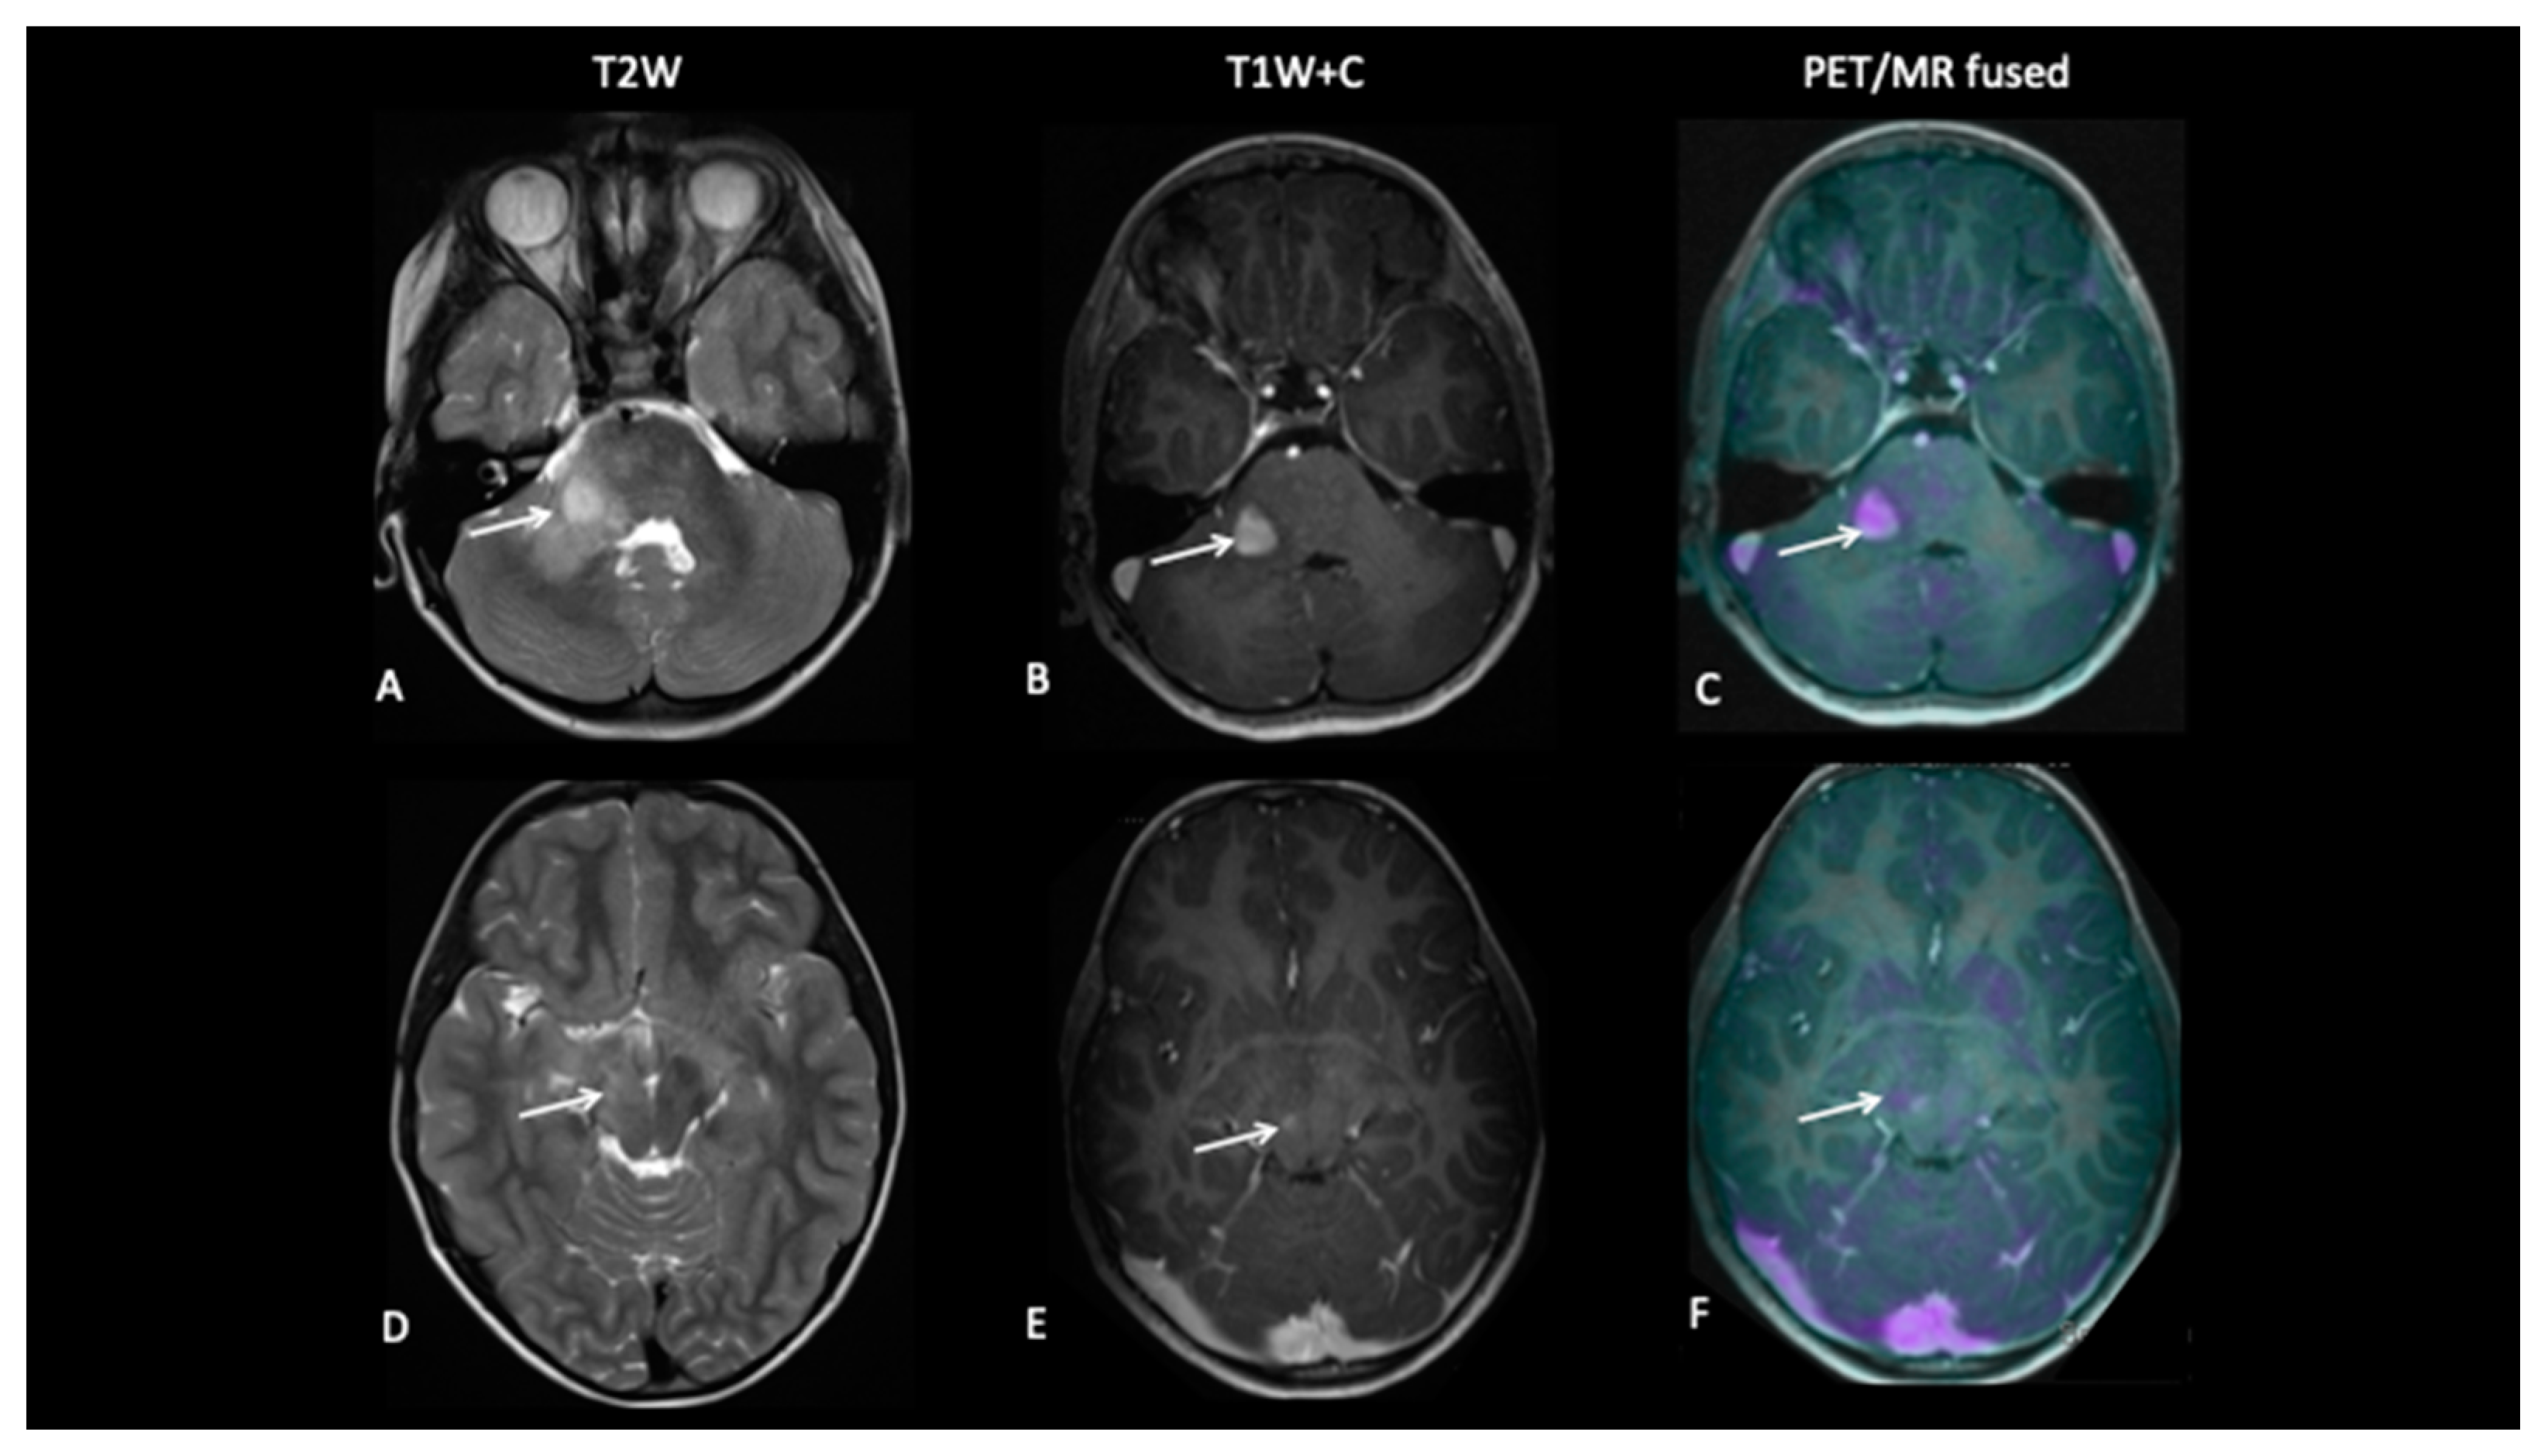

Figure 4.

At baseline, there is a large pontine tumour (A) with a dorsally exophytic enhancing component (B), which shows FCho avidity on the PET/MR fused image (C). Follow-up imaging demonstrates residual dorsal enhancement (D,E), but FCho confirms no avidity (F) consistent with complete metabolic response.

- Patient 2: Early Response Assessment

A 13-year-old female with a large tumour involving left thalamus and basal ganglia, infiltrating into the adjacent white matter, insular cortex and left aspect of the upper brain stem underwent a biopsy of the thalamic component, which confirmed high-grade astrocytoma with a mutation of the variant H3.3 gene. An early response assessment scan 6 weeks after completion of chemoradiotherapy demonstrated no residual enhancement in the tumour, but FDOPA PET showed residual tracer distribution consistent with residual metabolically active disease (Figure 5).

Figure 5.

At baseline, there is non-enhancing tumour involving the left basal ganglia (A,B) with 8F-fluorocholine (FCho) and 18fluoro-L-phenylalanine (FDOPA) avidity (C). Follow-up imaging shows residual non-enhancing tumour (D,E) reported as stable disease, but FDOPA PET demonstrates reduced uptake (F) consistent with metabolic partial response.